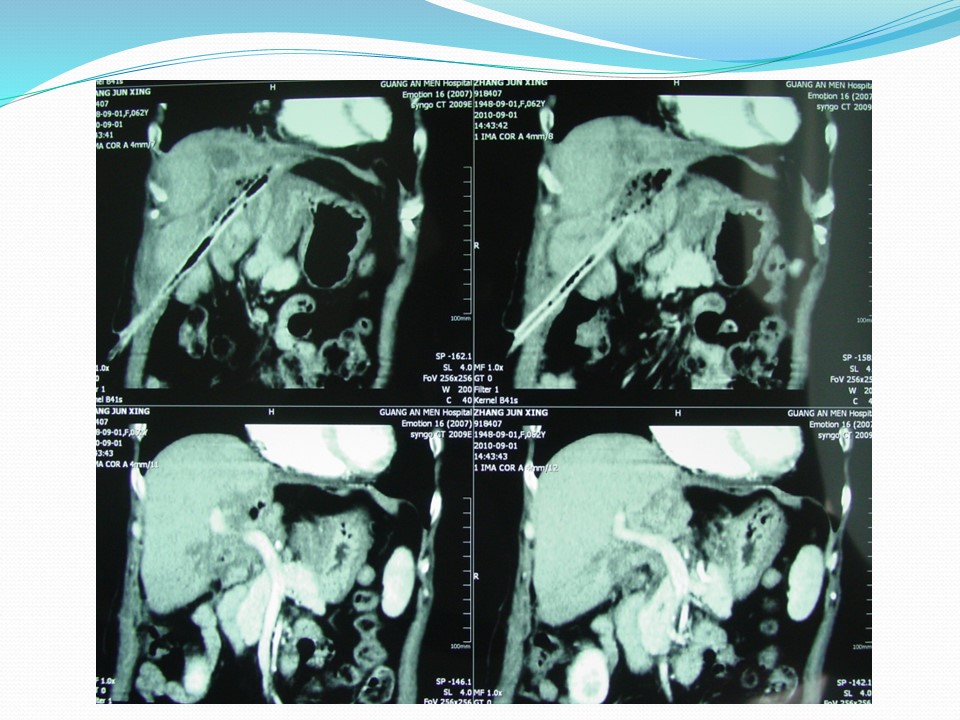

胆管癌外科治疗的实践和存在问题的探讨

Biliary duct cancer / Cholangiocarcinoma

定义:发生于肝外胆管(含左右肝管主干至胆总管下端)恶性肿瘤的总称。不包括肝内胆管癌、肝脏胆管细胞癌、胆囊癌、乏特壶腹癌。